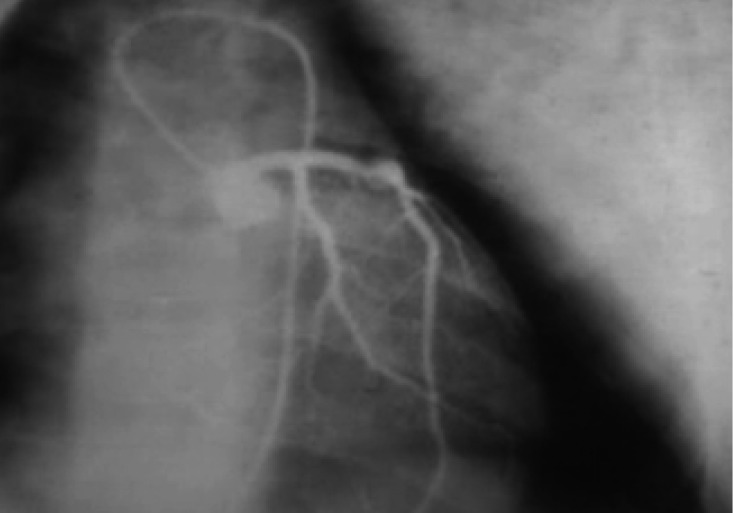

Figure 2

Left circumflex stenosis improved from 80% to <25% after PTCA.